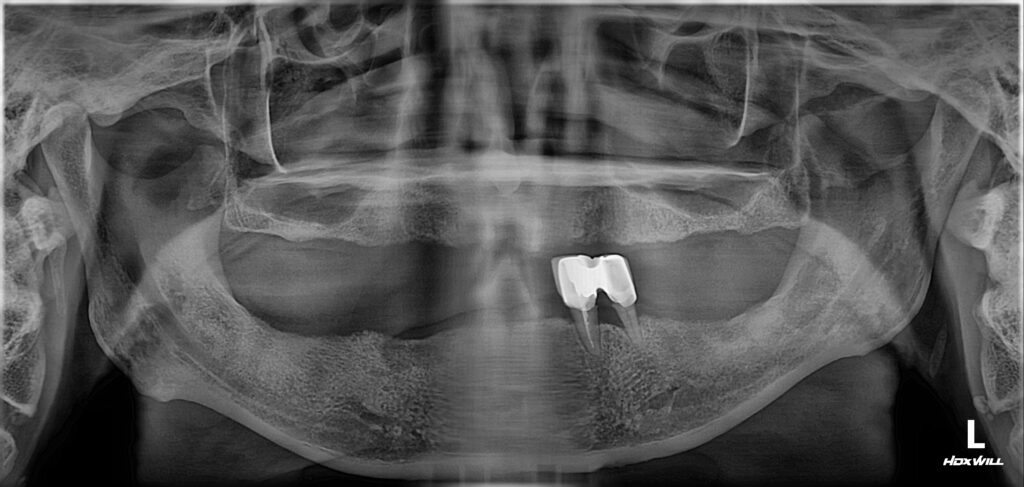

아래턱에 두 개의 치아만 남은 채 불편하게 틀니를 쓰고 계셨던 어르신께서 치과에 내원하셨습니다.

아래턱에 먼저 여섯 개 임플란트를 심었고요.​

​사진 : 아래는 임플란트 보철이 즉시 들어갔고, 위에는 임시틀니를 이용해서 식사를 가능케 해드린 모습.

아래는 임플란트를 이용하여 즉시 임시 보철을 만들어 드렸고 (탈착 안 해도 되는 고정식 보철)